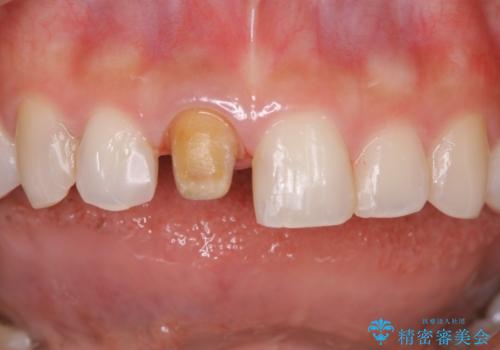

- 前歯一本だけ色が暗いことが気になりご相談にいらした患者様です。周辺の歯と色味をぴったり合わせることで自然な仕上がりになりました。